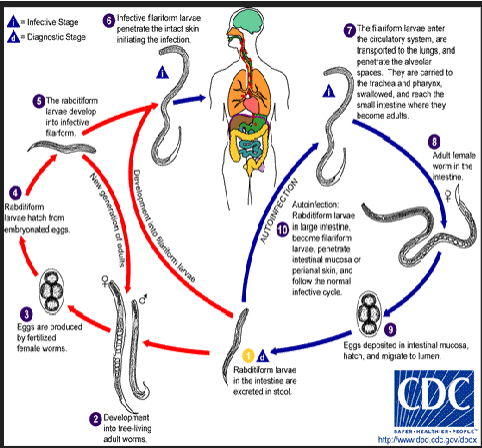

life cycle of strongyloides stercoralis (general)

Acquired by direct skin penetration or by ingestion of contaminated water (filariform larvae)

steps of s stercoralis life cycle

infective filariform larvae penetrate skin

autoinfection

filariform enter circulation or lungs where they are swallowed & enter small intestine

become adults in gut; adult female worm creates eggs in intestinal mucosa

eggs hatch into rhabditiform & develop into filariform & restart cycle

free-living

rhabditiform excreted in stool

develop into mature free living worms

worms make eggs & eggs r fertilized → rhabditiform hatch

rhabditiform → filariform → penetrate skin

(strongyloides stercoralis) autoinfection life cycle

Eggs laid in gut hatch into rhabditiform larvae

Mature into filariform larvae

Penetrate intestine, migrate to lung

Asexual reproduction

Only female worms present

(strongyloides stercoralis) free living life cycle

Rhabditiform larvae mature into 4th stage larvae, then adults

Mate, lay eggs, hatch rhabditiform

Larvae mature into filariform larvae that mature into adults

Sexual reproduction

Occurs in temperate climates

(strongyloides stercoralis) parasitic life cycle

Rhabditiform larvae hatch from egg, mature into filariform larvae

Penetrate intact skin of human host

Moves into the auto-infective cycle from there